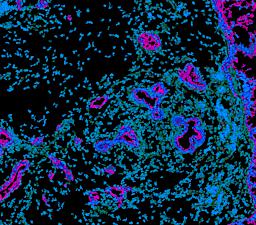

Pancreatic ductal adenocarcinoma is a lethal disease with limited treatment options and poor survival. We studied 83 spatial samples from 31 patients (11 treatment-naïve and 20 treated) using single-cell/nucleus RNA sequencing, bulk-proteogenomics, spatial transcriptomics and cellular imaging. Subpopulations of tumor cells exhibited signatures of proliferation, KRAS signaling, cell stress and epithelial-to-mesenchymal transition. Mapping mutations and copy number events distinguished tumor populations from normal and transitional cells, including acinar-to-ductal metaplasia and pancreatic intraepithelial neoplasia. Pathology-assisted deconvolution of spatial transcriptomic data identified tumor and transitional subpopulations with distinct histological features. We showed coordinated expression of TIGIT in exhausted and regulatory T cells and Nectin in tumor cells. Chemo-resistant samples contain a threefold enrichment of inflammatory cancer-associated fibroblasts that upregulate metallothioneins. Our study reveals a deeper understanding of the intricate substructure of pancreatic ductal adenocarcinoma tumors that could help improve therapy for patients with this disease.